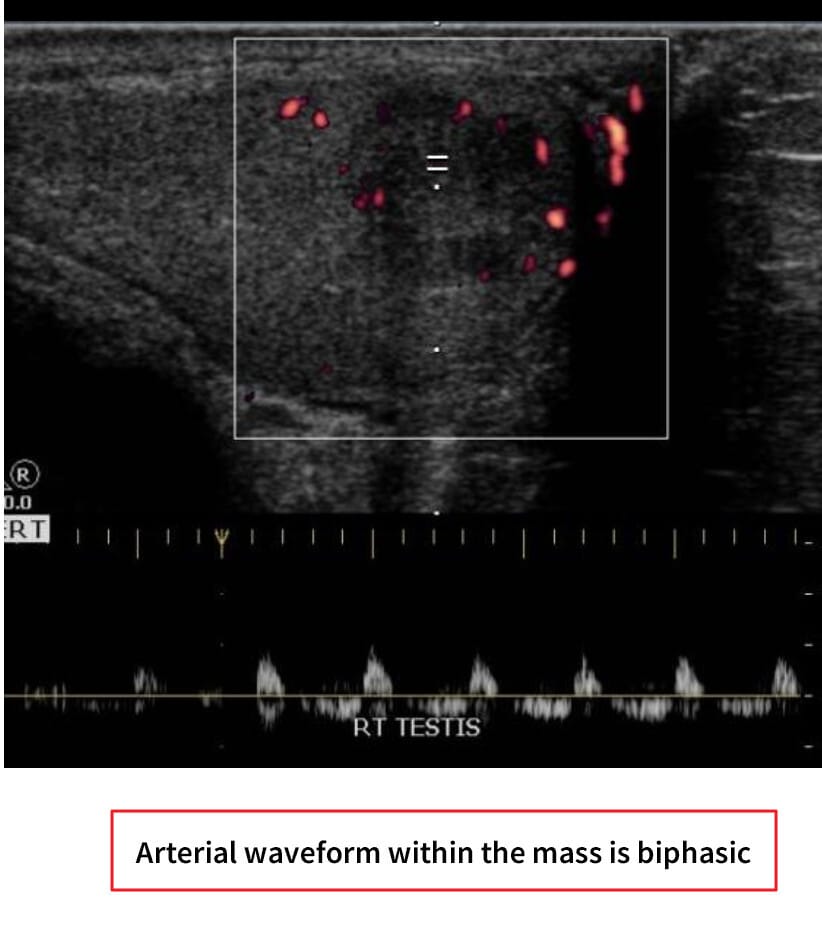

고환암 영상 소견

– 신체검사: 단단한 고환 종괴 촉지.

– 종양표지자: hCG 상승 가능, 그러나 AFP는 정상

– 영상검사: 고환 초음파에서 저에코성 종괴 확인.

– CT/MRI: 병기 설정 및 전이 평가.

– 확진: 고환 절제술(근치적 고환 절제술, radical orchiectomy)을 통한 조직학적 확인.